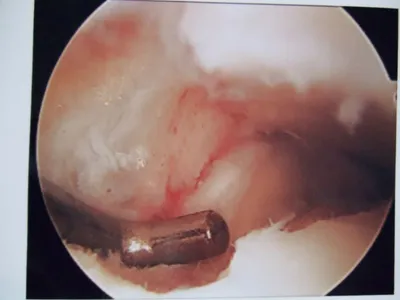

Pic after microfracture and debridement of above OCD.

Pic during microfracture of tibial OCD.